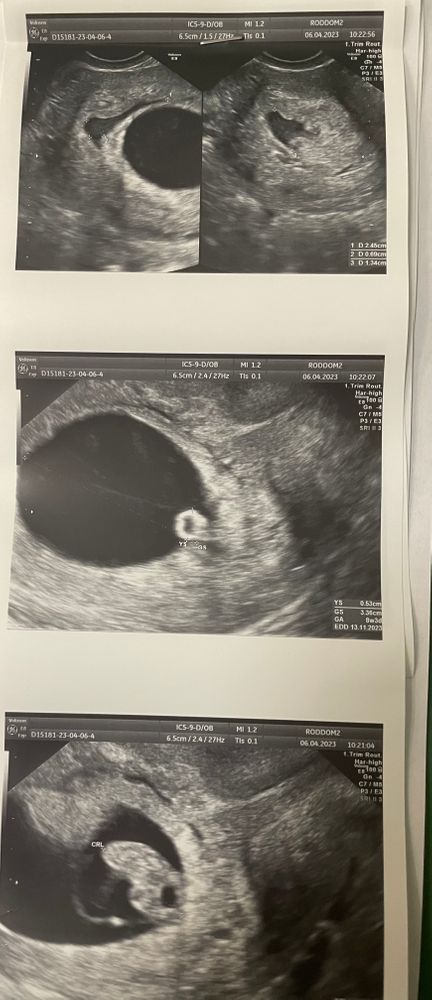

Ретрохориальная гематома 25*13*7 мм в стадии регрессии

Сама гематома на 1 снимке УЗИ. 2-3 это уже погодное яйцо с эмбрионом.